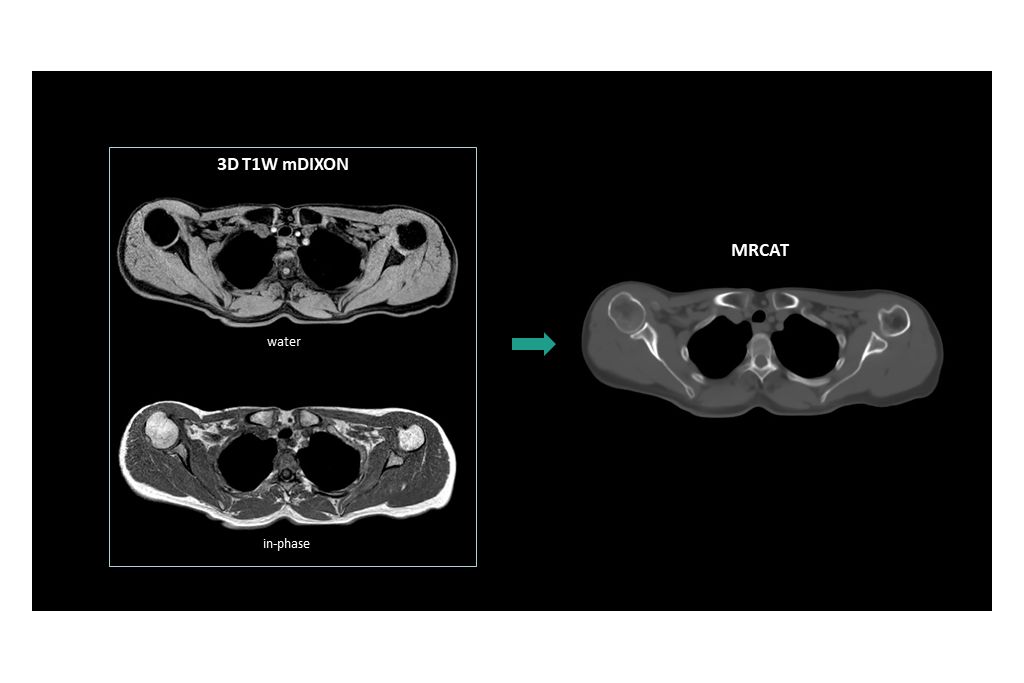

• MRCAT generation based on single mDIXON source scan

MRCAT generation based on single mDIXON source scan

Image acquisition is made easy by a dedicated ExamCard that includes a single, multi-contrast 3D T1W mDIXON scan, which is standardized to deliver consistent results and high geometric accuracy. The MRCAT Head and Neck scan can be acquired before or after contrast agent administration. Additional sequences, e.g. for delineation, can be easily added to the protocol to address your specific clinical needs.